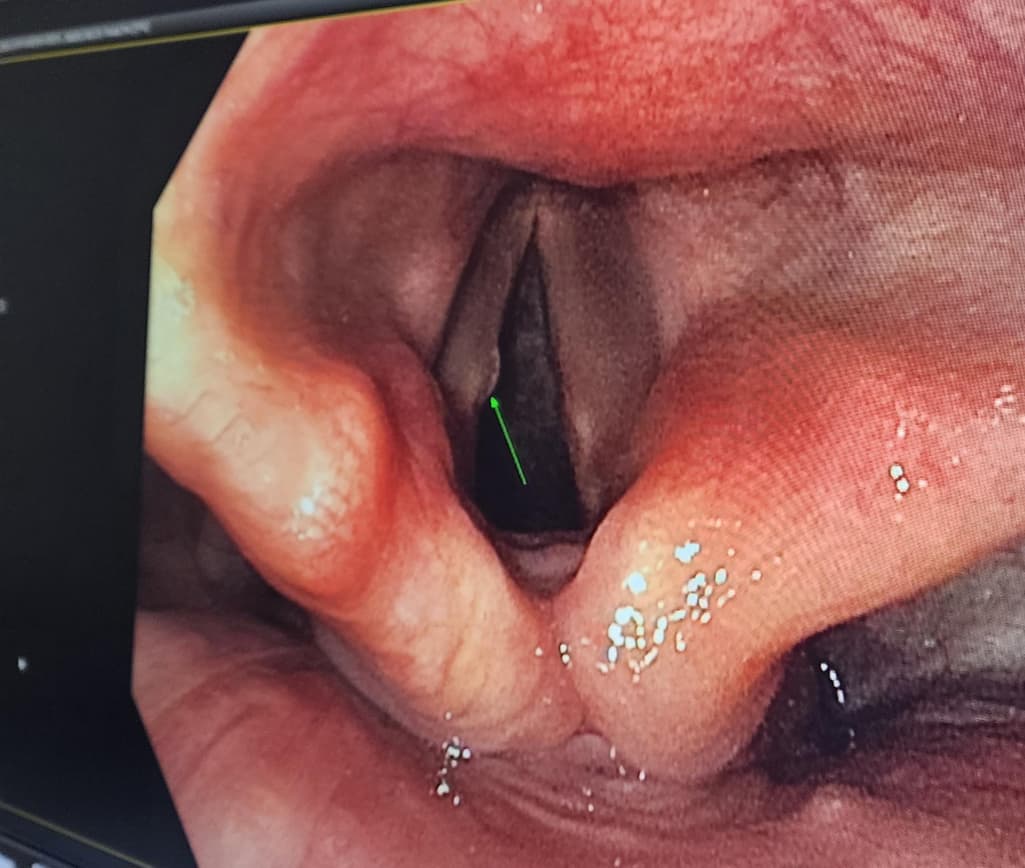

말씀하시는 성대결절로 인한 증상으로 보이지는 않습니다.

성대결절의 경우 생활습관변화, 주사치료등으로 치료가 가능합니다.

안녕하세요. 최규은 내과 전문의입니다.

사진상으로는 성대결절이 의심됩니다. 가까운 이비인후과에 방문하여 진료를 보시는게 좋겠습니다. 감사합니다.